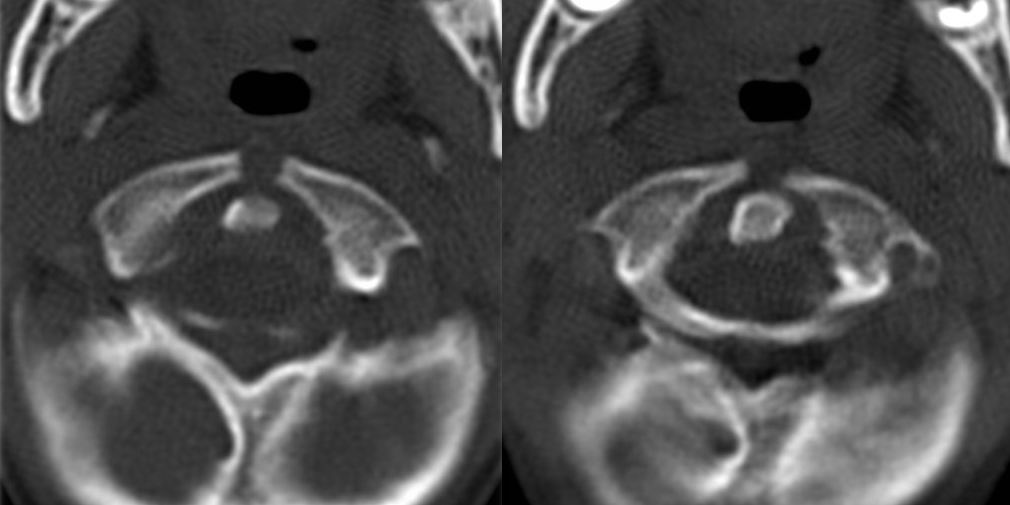

标题: PED1645:小孩寰椎问题

向各位请教:小孩子,6岁,寰椎两侧块前缘愈合了吗?不知道哪位老师能说说寰椎发育方面的问题.

环椎前弓裂

寰枢椎可以当做是独立于颈椎的一个部分,一般与枕骨相应结构称为枕寰枢复合体。寰椎有三个骨化中心,分别为前弓,后弓两侧,分别相当于颈胸腰椎椎体的椎体,双侧椎板。

发育过程为前弓出现齿突和双侧块骨化中心(特别说时,齿突在发育过程中是属于寰椎的,你可以把他当做“椎体“),后弓出现两侧骨化中心,齿突骨化后脱离前弓骨化中必与枢椎的齿突融合(这就是为什么会出现游离齿突的原因),齿突脱离时其其方还有剩余的软骨,此时两侧块前部也在向前骨化,当骨化完全时就形成齿突前结节,当不完全时就形成前弓裂(相当于我们平常诊断的如腰骶椎隐裂一样),同样,后弓也可以形成这样的裂隙。后弓与侧块联合处为椎动脉沟,此处有时可形成寰椎后弓桥(也有叫后弓孔、弓沟的)

寰椎骨化一般可以到10—12岁,所以现在在下结论说隐裂或发育异常为时尚早。